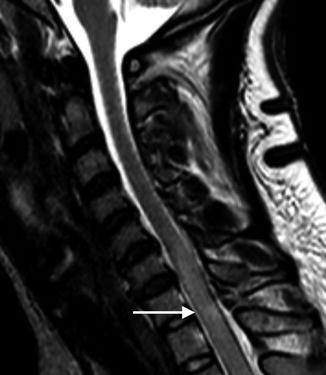

Sagittal T2-weighted MR image reveals abnormal cord signal indicative of cord contusion/edema (arrow) that was not apparent by CT